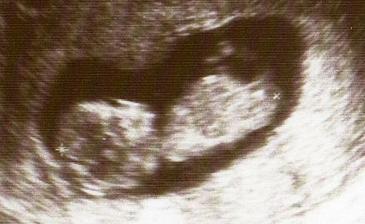

Listopad 08-screening 1.trimestru dopadl dobře.